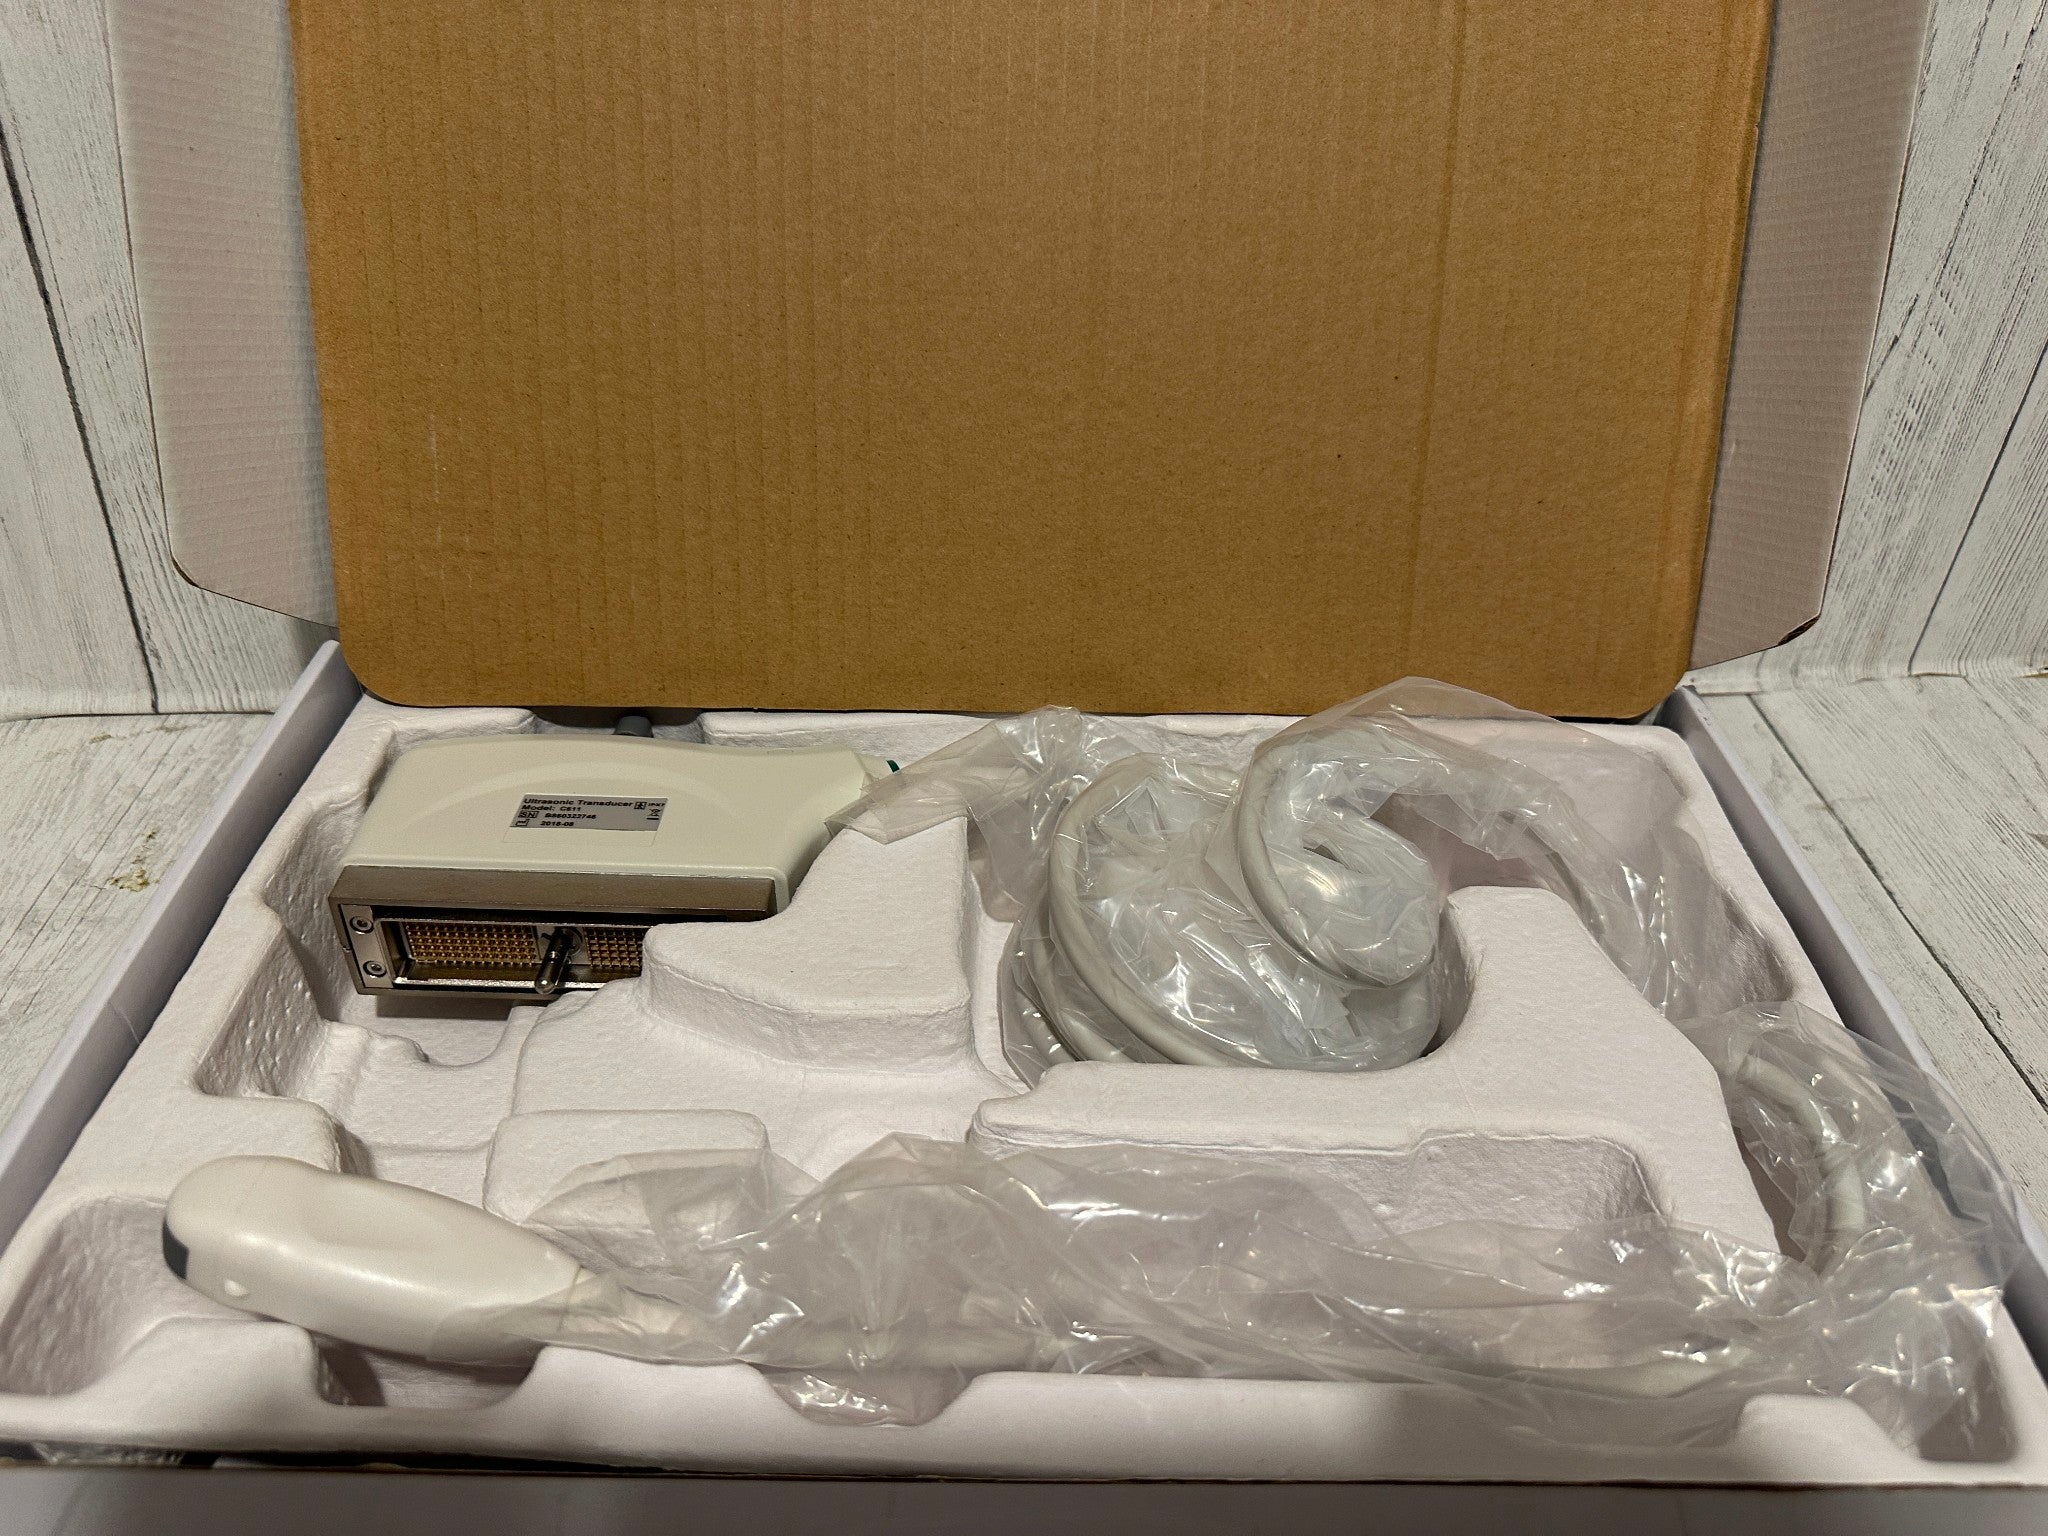

DIAGNOSTIC ULTRASOUND MACHINES FOR SALE

Mindray M9 Portable Ultrasound With 2 Probes

Sale price$ 22,302.88